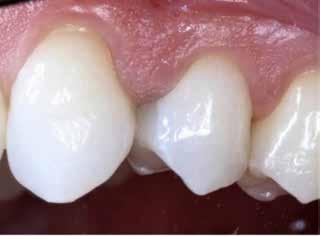

En dybtliggende amalgam-misfarvning udgør en af de mest vanskelige udfordringer ved udskiftning af restaureringer. Transcend Universal Body farven blev anvendt til at erstatte amalgamen, uden brug af blokeringsmateriale. Bemærk, hvor fremragende farven blender ind i den bevarede crista obliqua.

Før Efter